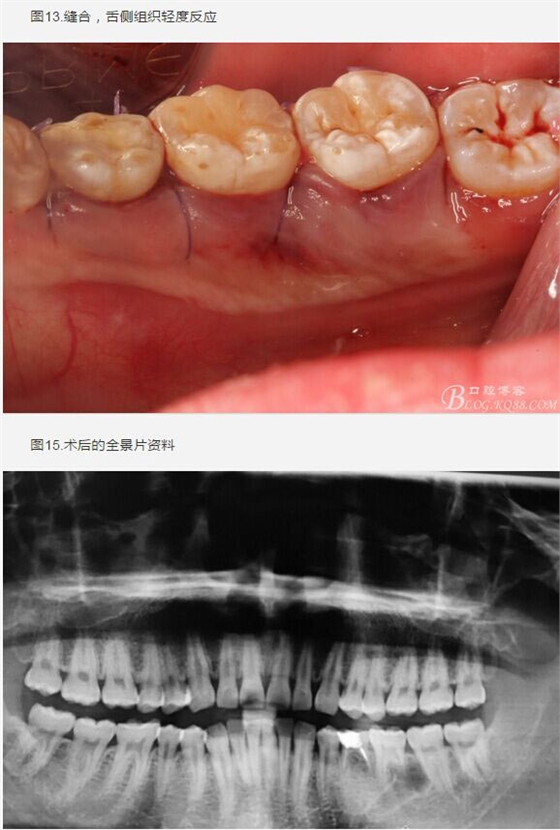

圖1.術(shù)前的全景片影像檢查,35移位至36、37之間。